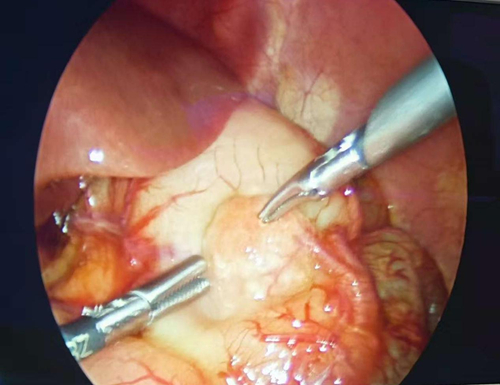

李炳根副主任医师领衔的小儿外科手术团队迎难而上,在高清腹腔镜的放大视野下,小心翼翼地分离组织,精准地暴露梗阻部位。手术过程不仅成功完成了十二指肠菱形吻合术(一种可最大限度保留肠道功能、减少术后并发症的先进术式),更有了两个关键发现。一是发现了导致本次梗阻的“元凶”——环状胰腺:即一部分胰腺组织像戒指一样环绕并压迫十二指肠,导致其不通;二是在胃区发现了一处“异位胰腺”:这是一种先天性异常,团队也一并进行了妥善处理。

整台手术出血极少,在高难度的精细操作下,完美解除了肠道梗阻,为患儿打通了生命的“营养之路”。